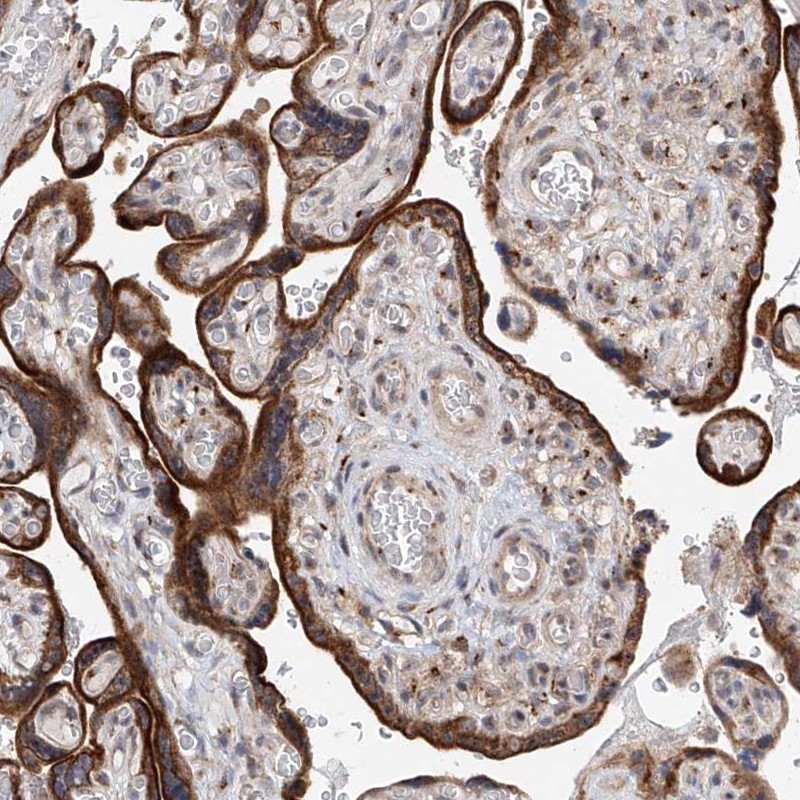

Immunohistochemical staining of human placenta shows cytoplasmic positivity in trophoblastic cells.